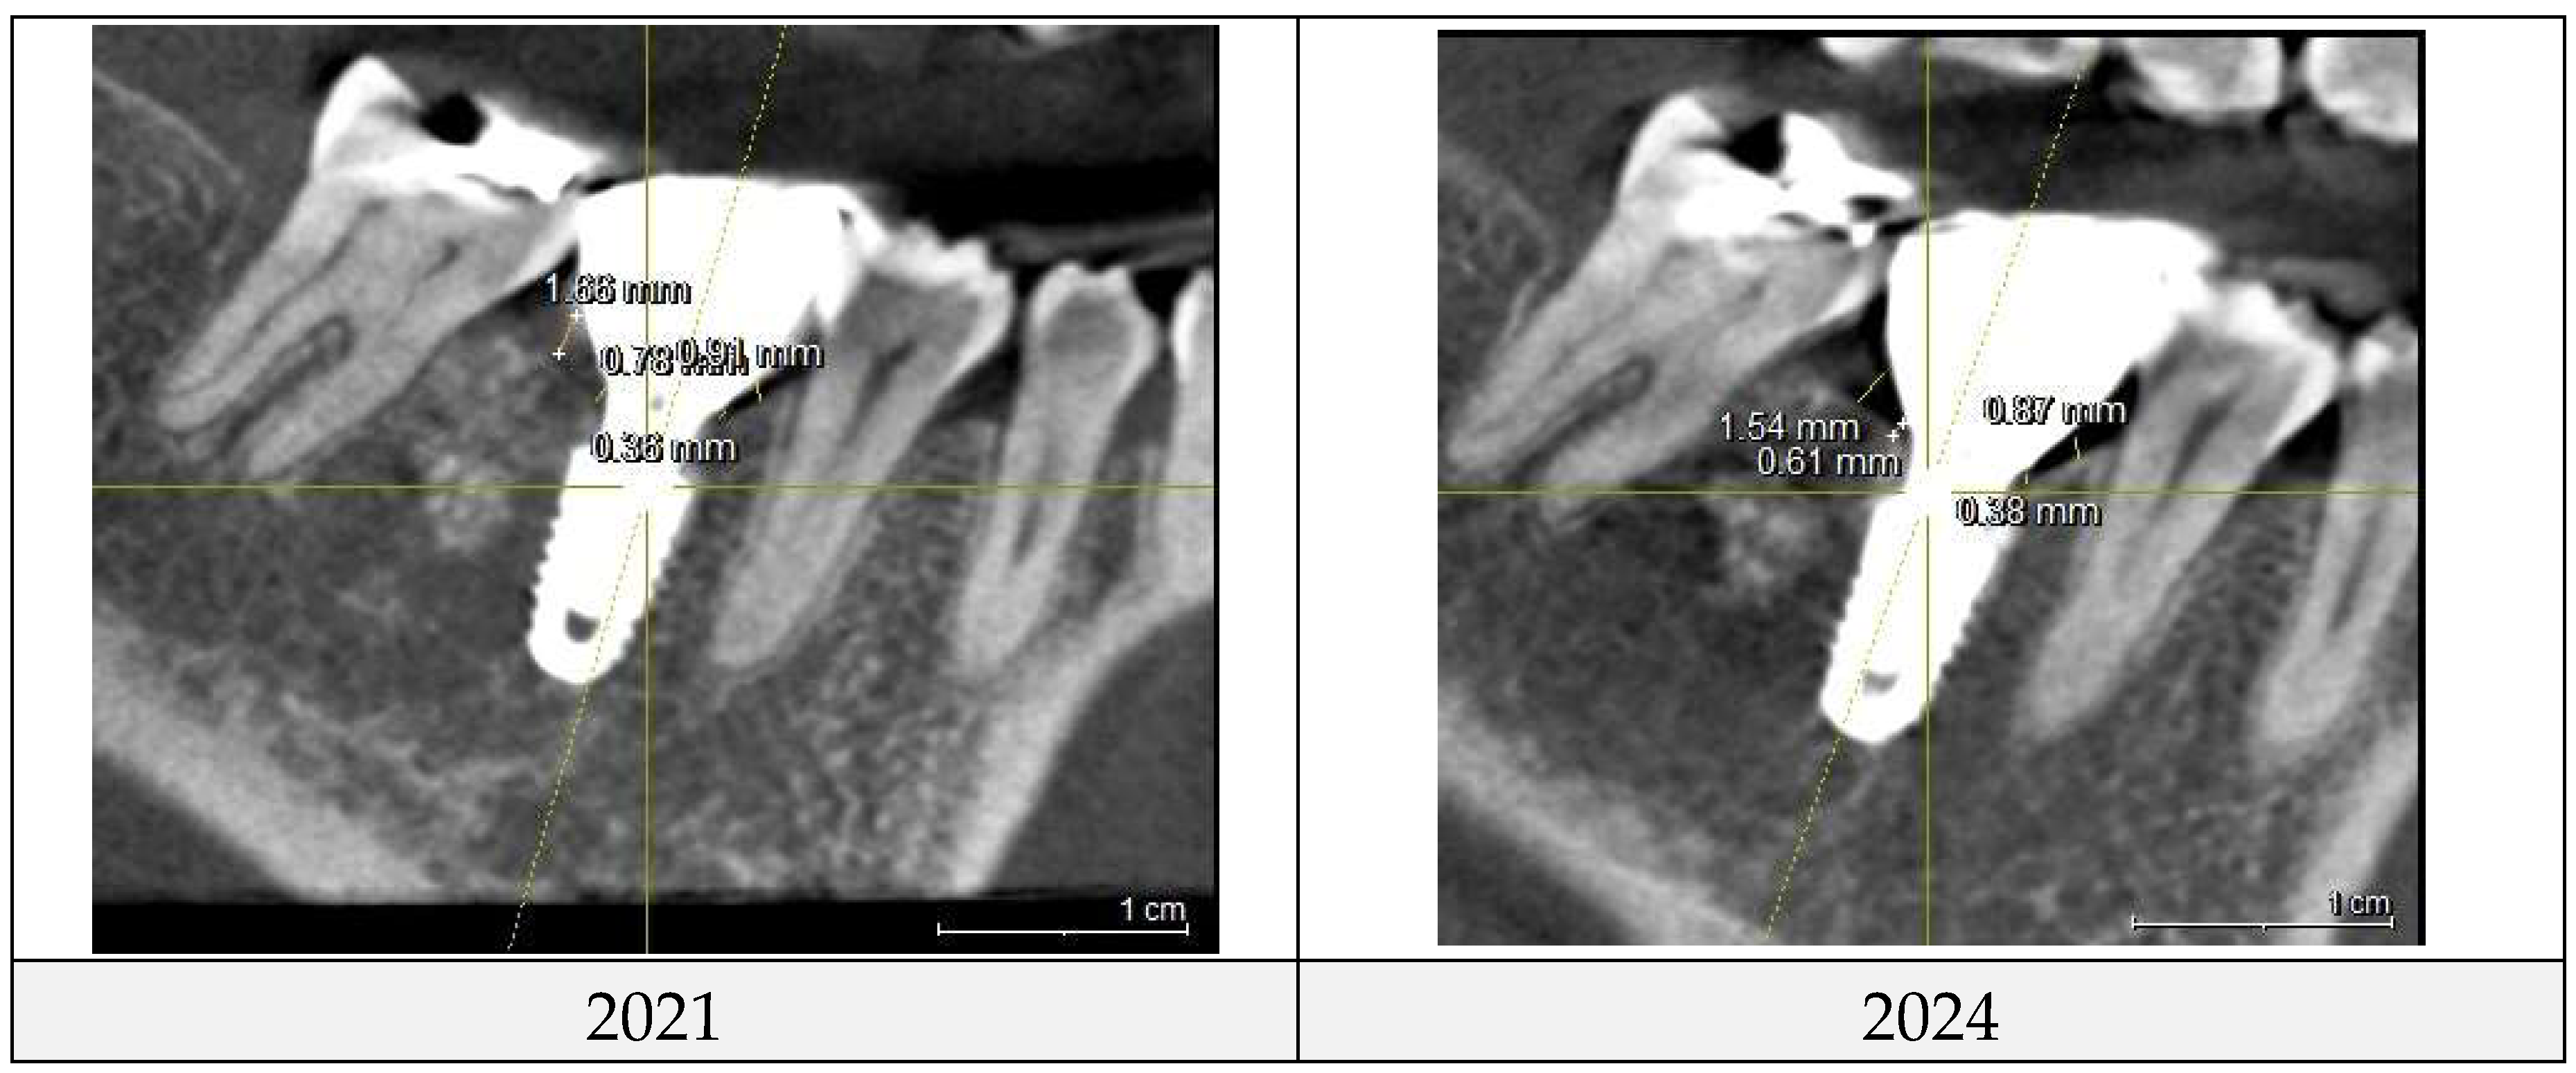

The two implant sites were analyzed in a split-mouth study using CBCT scans from 2021 and 2024 to assess peri-implant soft tissue and bone structure. CRD and DP measurements were obtained through CBCT imaging and clinical evaluations to examine their correlation with peri-implant health, particularly in managing peri-implant mucositis.

CRD and DP measurements for the upper left and lower right first molar implants were recorded in 2021 and 2024. Averages were calculated and compared over time, with results summarized in

Control site (the lower right 1st molar) for comparison

Changes of CRD

| pCRD |

2021 |

2024 |

changes |

| M |

0.91 |

0.87 |

-0.04 |

| D |

1.66 |

1.54 |

-0.12 |

| B |

0.3 |

0.34 |

0.04 |

| L |

1.41 |

1.15 |

-0.26 |

| average |

1.07 |

0.98 |

-0.10 |

| cCRD |

0.36 |

0.38 |

0.02 |

0.78 |

0.61 |

-0.17 |

0.21 |

-0.09 |

0.6 |

0.51 |

0.43 |

-0.08 |

Figure 7 and

Figure 8 illustrate the radiographic changes observed from 2021 to 2024 at the lower right first molar implant site (control site) and the upper left first molar implant site (experimental site), respectively. (

Figure 7,

Figure 7.

This image illustrates the X-ray measurements conducted on the lower right first molar implant, comparing data from 2021 and 2024.